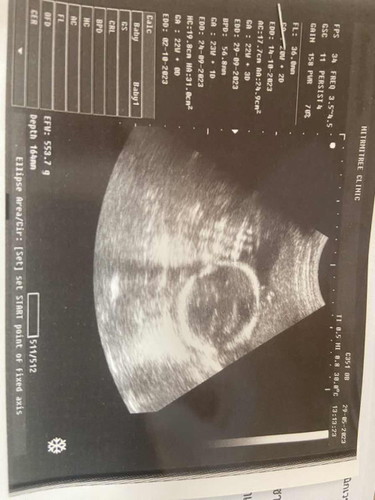

ช่วยดูเพศหน่อยค่าา ❤️

คุณหมอบอกได้ลูกชาย 🥰 คุณพ่ออยากได้ลูกสาว😂 แม่อยากได้ลูกชาย 😂

กำลังจะเป็นแม่